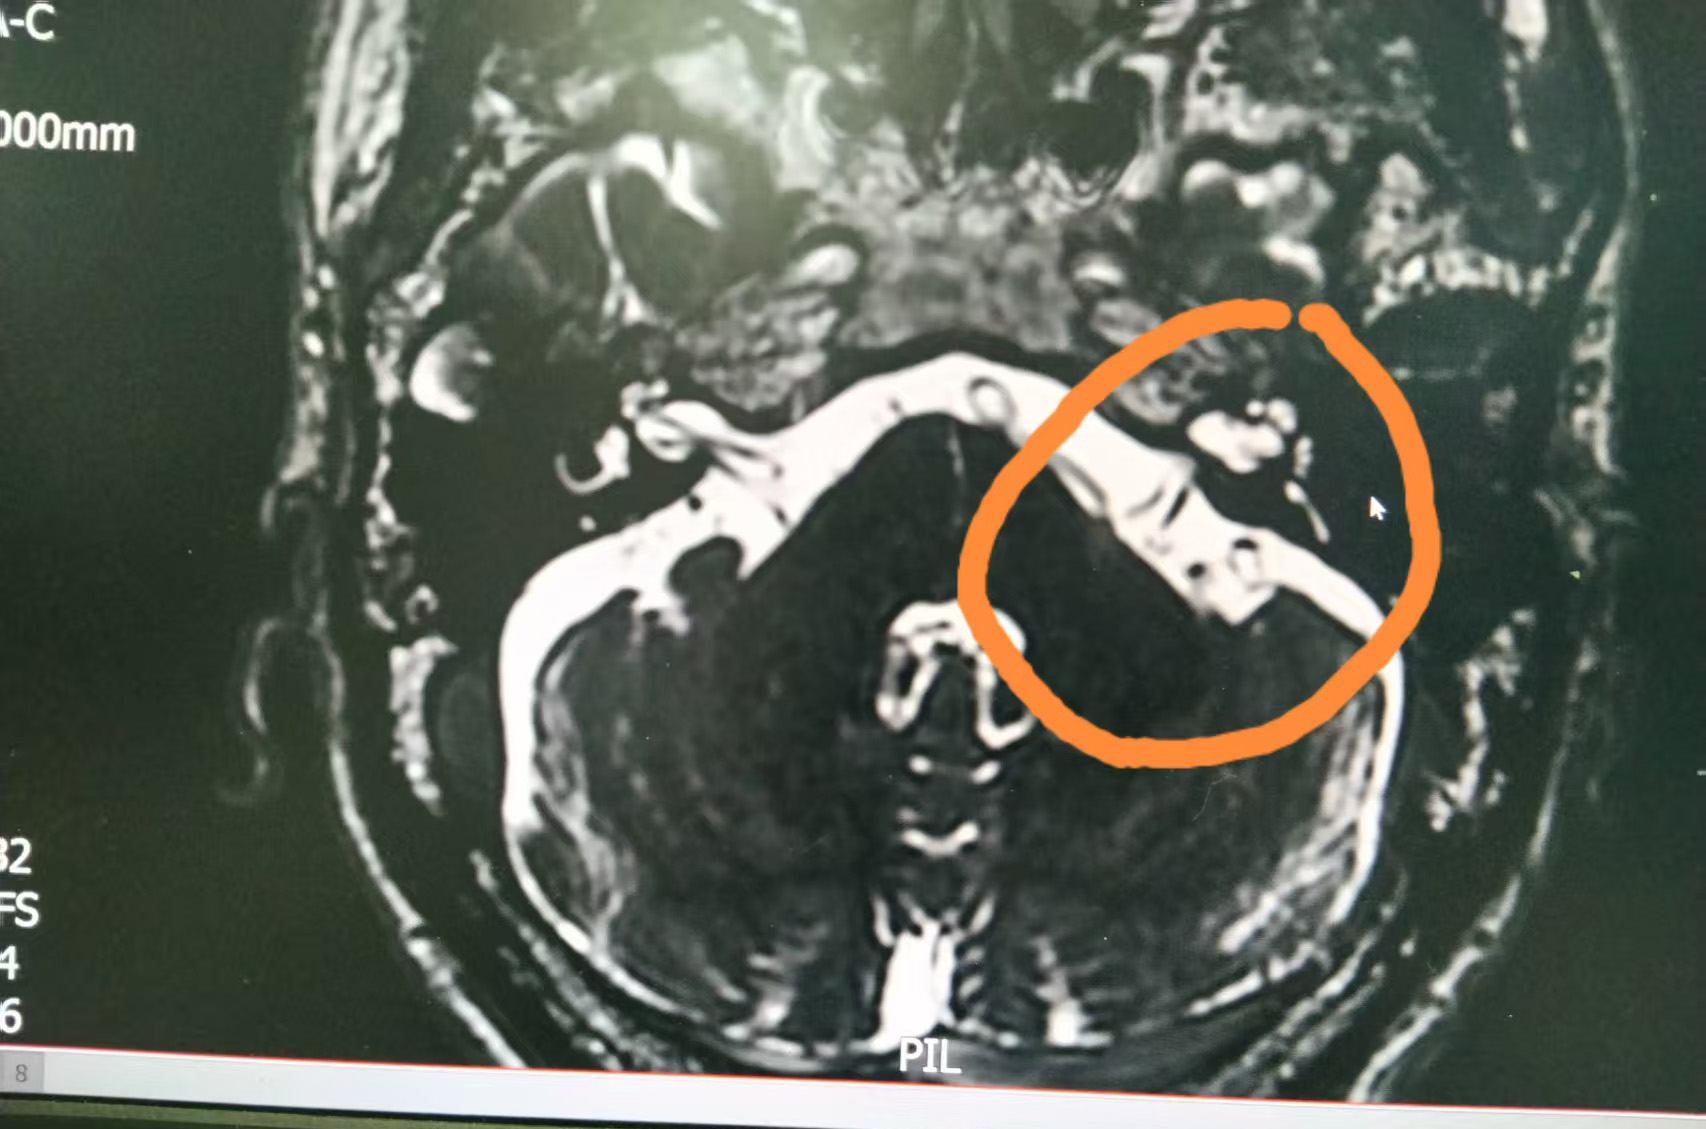

近日,黄先生来到仙桃一医就诊。神经外科团队接诊后为其完善磁共振平扫等相关检查,结合患者主诉及高血压病史,初步诊断其为面肌痉挛、高血压病3级(高危)。

10月12日20时25分,蒋伟副院长带领仙桃一医神经外科孙道法副主任医师、刘宙鹏主治医师等正式开始手术。手术团队经左侧耳后切口精准开颅,探查发现患者面神经近脑干区被血管襻缠绕,这正是致病根源。